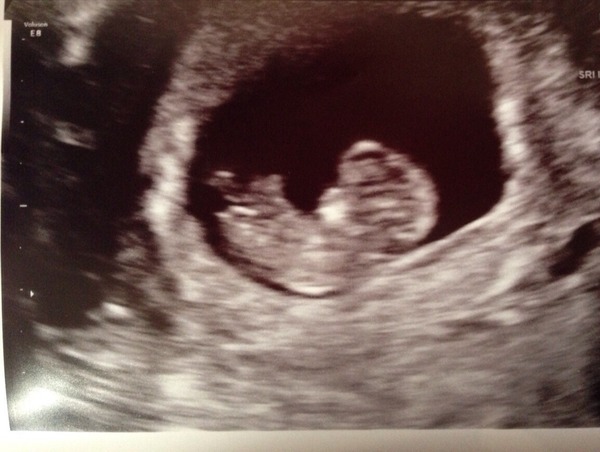

Just to update that I had an early scan today at 9w and everything is perfect. I am over the moon and cried Grin

Thanks stubborn and Lola. I have a scan pic!! I can start looking at blankets and prams and stuff. I'm so EXCITED!!!! Grin